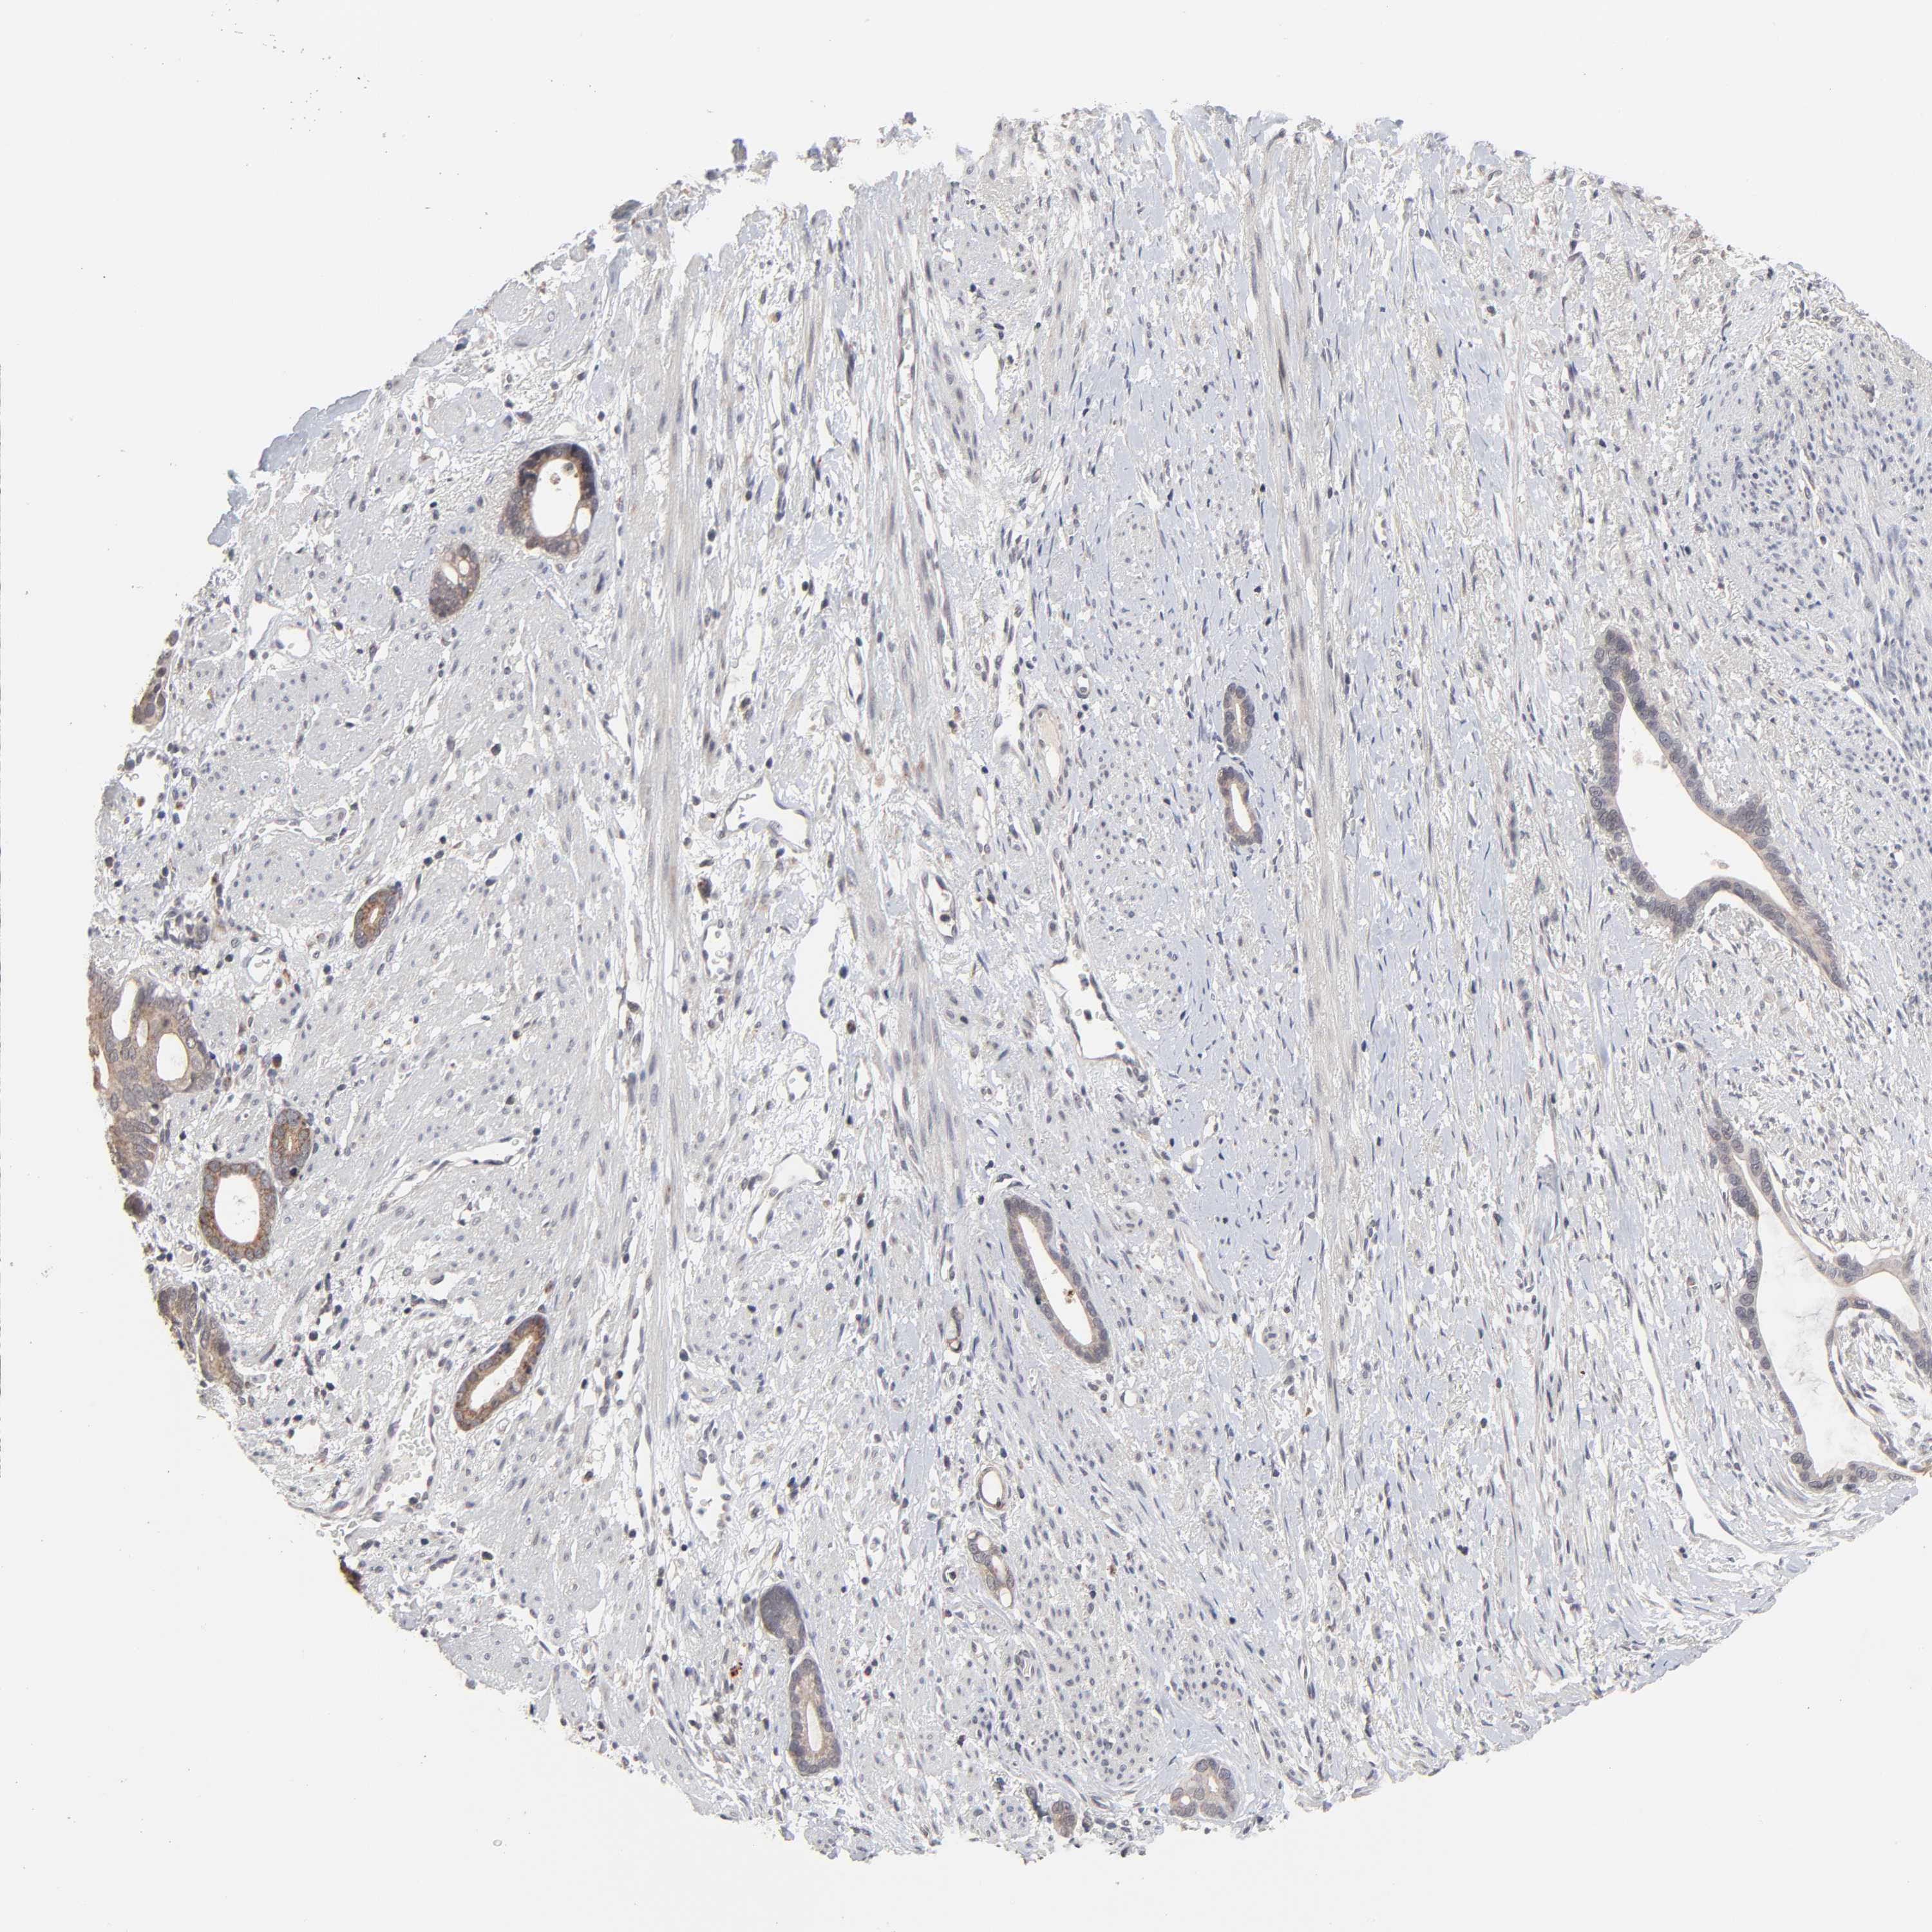

STOMACH CANCER - Protein expressioni

A mouse-over function shows sample information and annotation data. Click on an image to view it in a full screen mode. Samples can be filtered based on level of antibody staining by selecting one or several of the following categories: high, medium, low and not detected. The assay and annotation is described here.

Antibody stainingi

Antibody staining in the annotated cell types in the current human tissue is reported as not detected, low, medium, or high, based on conventional immunohistochemistry profiling in selected tissues. This score is based on the combination of the staining intensity and fraction of stained cells.

Each image is clickable and will lead to virtual microscopy that enables deeper exploration of all samples and also displays staining intensity scores, fraction scores and subcellular localization as well as patient and tissue information for each sample.

Antibody HPA004171

Staining

High

Medium

Low

Not detected

Intensity

Strong

Moderate

Weak

Negative

Quantity

>75%

75%-25%

<25%

None

Location

Nuclear

Cytoplasmic/membranous

Cytoplasmic/membranous,nuclear

Adenocarcinoma, NOS

Adenocarcinoma, High grade